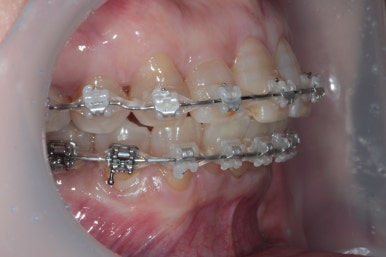

상당히 뻐드러져 있었던 앞니가 적절한 위치를 찾아가고 있는지 확인을 하기 위해 측면 사진도 찍어봅니다.

저희 치과에서는 Overjet이라고 표현하는데, 윗니가 아랫니를 약 1-2mm 정도 덮는 모양이어야 평균이라고 봅니다.

보시면 위와 아래 치아 사이에 약간의 틈이 있는 것을 보실 수 있죠? 점점 개선될거에요!!

그리고 교합면 사진을 통해 전체적인 진행 상태도 파악할 수 있죠.